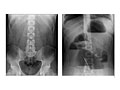

An abdominal X-ray is a picture of structures and organs in the belly (abdomen). This includes the stomach, liver, spleen, and large and small intestines. It also includes the diaphragm, which is the muscle that separates the chest and belly areas. Often two X-rays will be taken from different positions. If the test is being done to look for certain problems of the kidneys or bladder, it is often called a KUB (for kidneys, ureters, and bladder).

Often two pictures are taken: one while you are lying down (supine) and the other one while you are standing (erect view). If you are not able to stand, the X-ray may be taken while you lie on your side with your arm over your head.